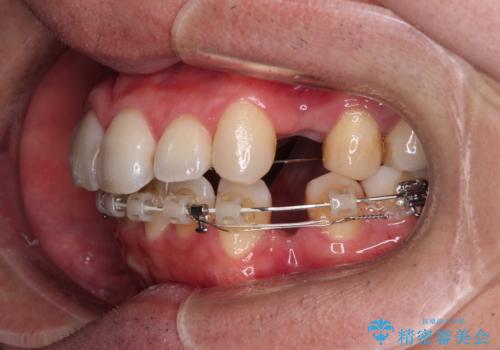

- 矯正装置

- ハーフリンガル

裏側装置での交叉咬合改善は非常に困難なもので、頻繁に装置の脱落がありました。

それでも想定以上に治療期間は長期化せず、咬み合わせも口元も満足のいく仕上がりとなりました。